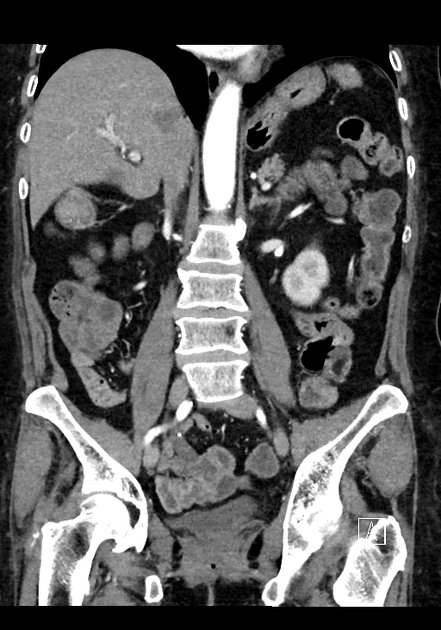

CT Bleeding Study

4 views

Jan 20, 2025

A patient presents with acute hypotension and hematochezia. An estimated 2L of blood loss was recorded in the ED. The patient was referred to general surgery. The bleeding stopped, and the patient remained hemodynamically stable. A colonoscopy was arranged. CT findings suggest an unusual cause of lower gastrointestinal bleeding. Based on the provided CT scan and case history, what is the most likely diagnosis?

Correct answer is Appendiceal hemorrhage due to angiodysplasia